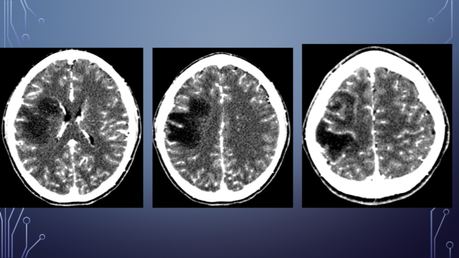

PA: Inicia hace 5 meses con amnesia, cefalea generalizada la cual empeora con el ejercicio, agregándose parálisis facial izquierda por lo que acude con neurólogo privado solicitando TC y posteriormente RM.

El paciente es diagnosticado con EM.